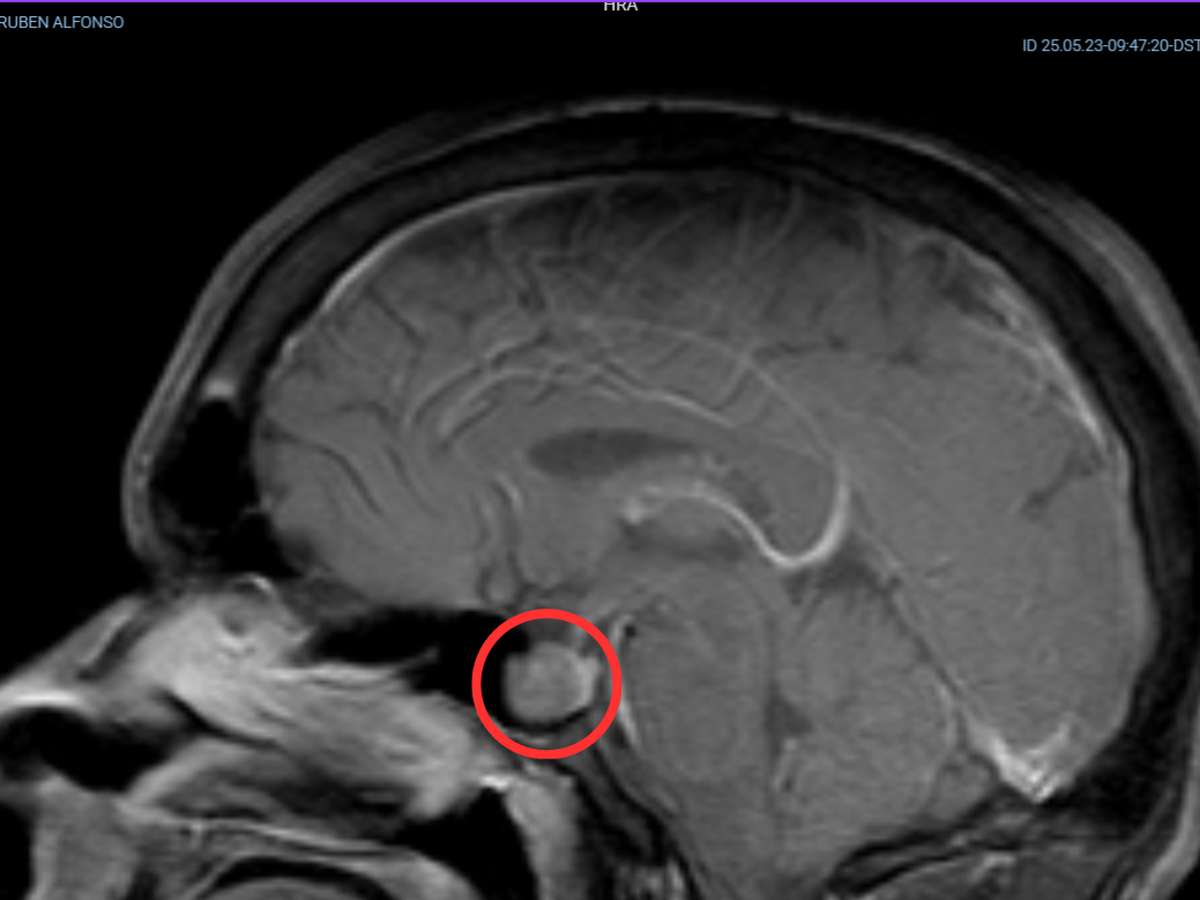

Una resonancia magnética de cráneo confirmó el diagnóstico: tengo un tumor en mi cerebro, en la glándula pituitaria (también conocida como hipófisis).

Después de varios estudios, se identificó que el tumor secreta hormona de crecimiento (GH) y hormona adrenocorticotrópica (ACTH), que estimulan la producción de IGF-1 y cortisol, respectivamente. Esta sobreproducción causa dos enfermedades simultáneas en mí: el exceso de GH provoca acromegalia, y el exceso de cortisol, enfermedad de Cushing.

Requiero de neurocirugía para extirpar el tumor, y después debo realizar un seguimiento hormonal con un endocrinólogo, además de resonancias magnéticas periódicas para ver si hay remisión.